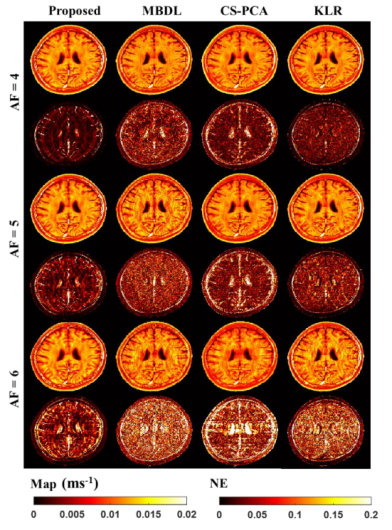

另外,研究团队最近还召开了关于快速定量磁共振参数成像的研究。在利用稀疏性加速定量磁共振参数成像的时候,由于其稀疏表示能力有限,细节混有噪声和伪影,在非线性滤波时会同时被滤除,导致加速度较大时模糊和细节丢失。针对这个问题,研究团队提出了基于非线性流形学习和正则化原像约束的快速定量磁共振参数成像算法。该方法创新性地假设待重建的图像是在高维欧几里得空间中稀疏采样的低维流形,并顺利获得使用核函数和稀疏编码技术将图像重建问题转化为高维欧氏空间中流形结构的嵌入映射问题,最终利用正则化约束技术从高度欠采样和噪声污染的K空间数据中精确重建定量磁共振图像。这一成果率先将基于压缩感知(Compressed Sensing,CS)理论的经典快速定量磁共振参数成像方法从线性空间扩展到非线性空间,有效保护了高加速倍数下重建定量磁共振参数图像的细节特征。实验结果表明:所提出算法不仅能够给予清晰的解剖结构,而且有效地提高了在体T2定量参数图像的估计精度,为快速定量磁共振参数成像给予了一种有效的解决策略(如图3所示)。相关研究工作是与香港养和医院研究部研究主任周谊航博士召开合作,在生物医学工程领域知名期刊IEEE Transactions on Biomedical Engineering上发表题为"Accelerating MR Parameter Mapping Using Nonlinear Compressive Manifold Learning and Regularized Pre-Imaging"(DOI:10.1109/TBME.2022.3158904)的研究成果。

图3. 基于非线性流形学习和正则化原像约束的快速定量磁共振参数成像